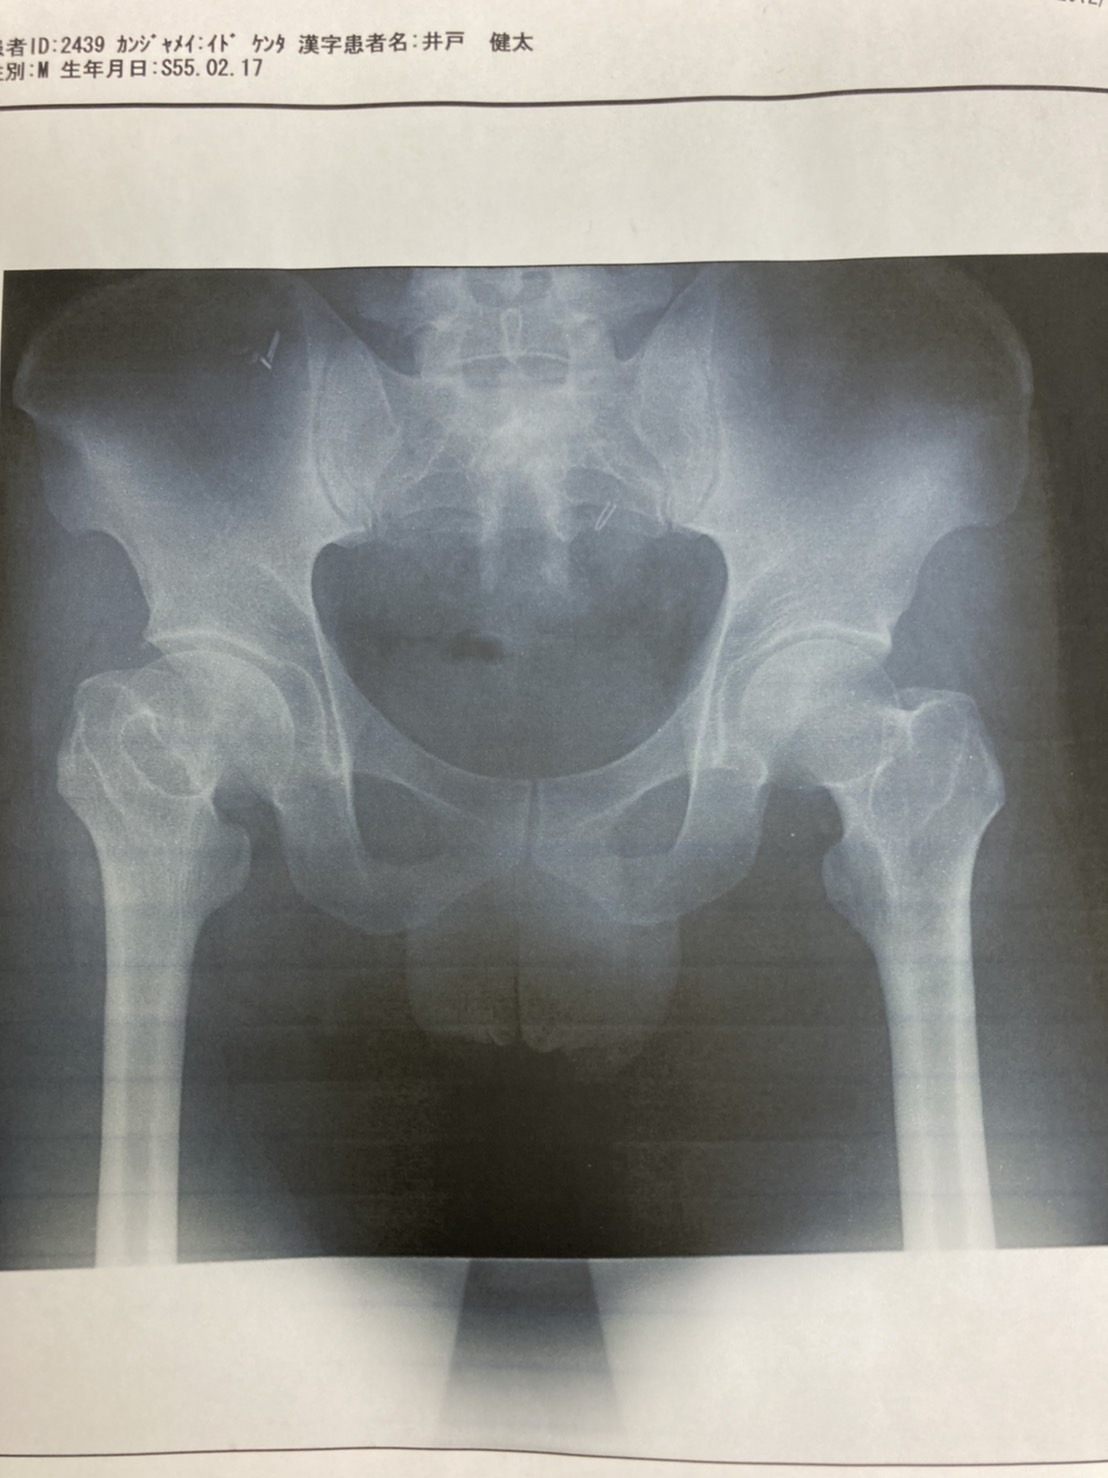

変形性関節症について

ピラティスは第一次世界大戦の時に負傷兵のためにリハビリとして考えられた運動です。東海地方ではまだマシンを使ったピラティスは珍しいエクササイズですが東京や関東などでは身体を維持する目的や腰痛研究の最前線のリハビリ、変形性股 […]